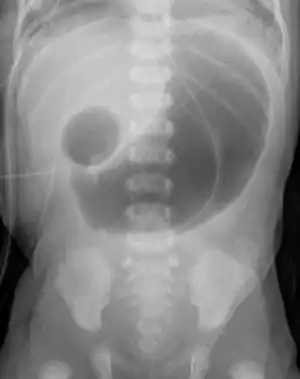

| Radiograph with double bubble sign indicating duodenal atresia | |